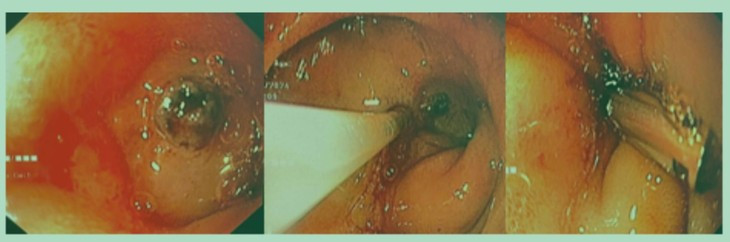

Vừa qua, ekip nội soi Tiêu hoá của bệnh viện Nhi đồng 2 đã tiến hành nội soi kẹp clip cầm máu thành công cho bệnh nhân xuất huyết tiêu hoá nặng do loét tá tràng.

Qua nội soi, bác sĩ thấy ổ loét lớn có máu tươi phun thành tia ở tá tràng. Ekip đã dùng clip kẹp kết hợp tiêm cầm máu ổ loét. Sau 30 phút, bệnh nhi đã ngưng xuất huyết.

Ổ loét trước và sau cầm máu cho bệnh nhi. Ảnh BVCC